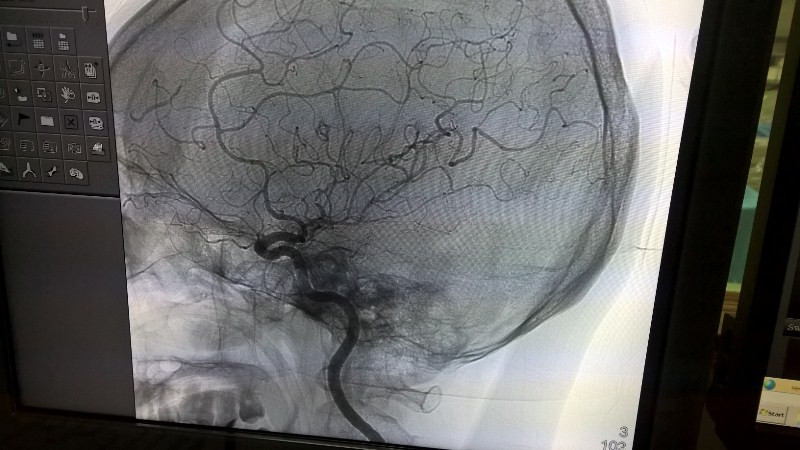

Chụp tổng quát mạch máu não (DSA) bằng kỹ thuật tiên tiến nhất hiện nay của thế giới.

Sau phẫu thuật, bệnh nhân tỉnh táo, hồi phục dần nhưng nguy được chẩn đoán có xu hướng phù não nên tiếp tục được can thiệp, chụp tổng quát mạch máu não (DSA) bằng kỹ thuật tiên tiến nhất hiện nay của thế giới.